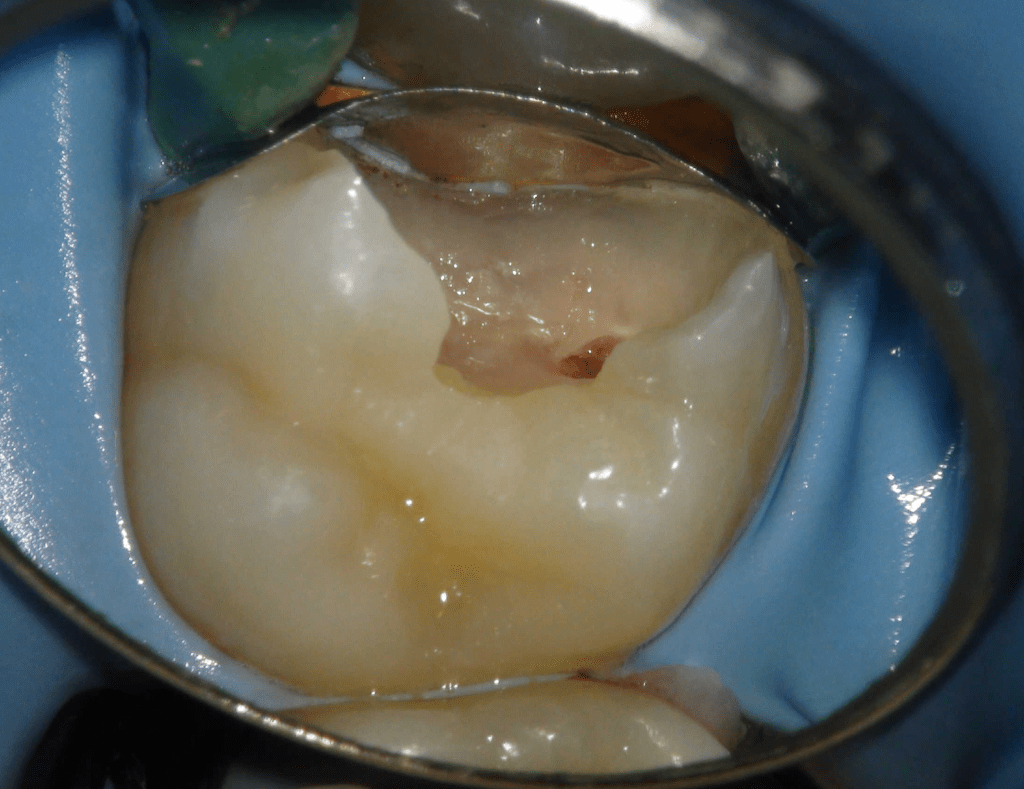

Pulpotomía biodentine + reco preendio